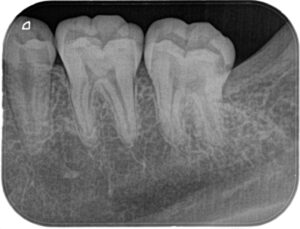

親知らずを抜いた後に小さいX線写真を撮ると第二大臼歯遠心に大きな虫歯がはっきりと写ってきました(下の赤い部分が虫歯です)